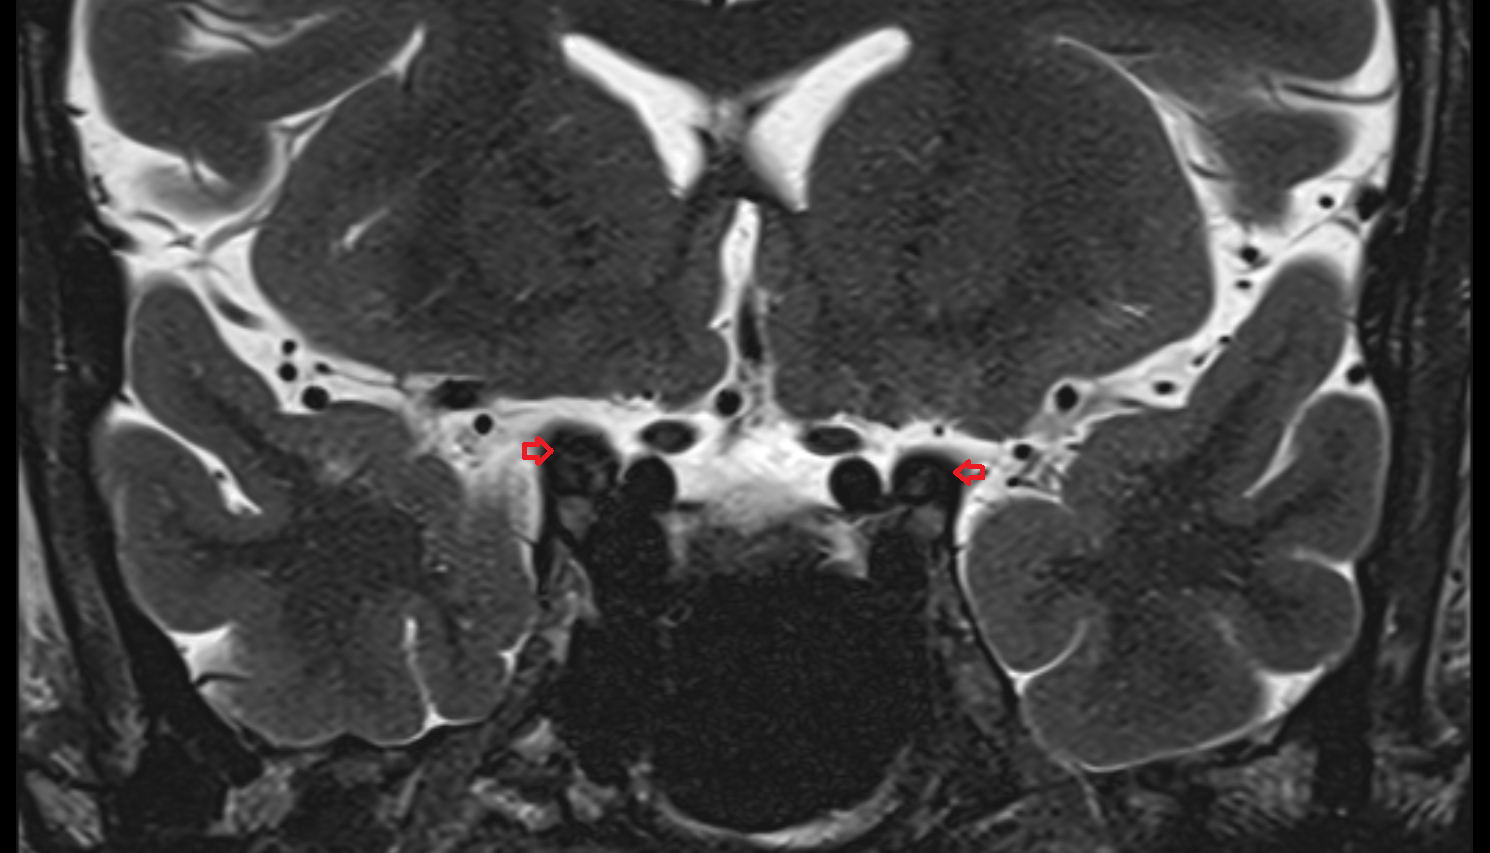

- Mandibular condyle

- Mandibular fossa

- Articular disc of temporomandibular joint

- Anterior Band of Articular Disc TMJ

- Posterior band of articular disc, TMJ

- Intermediate zone of articular disc

- Superior retrodiscal layer

- Superior synovial membrane of temporomandibular joint

- Temporomandibular joint